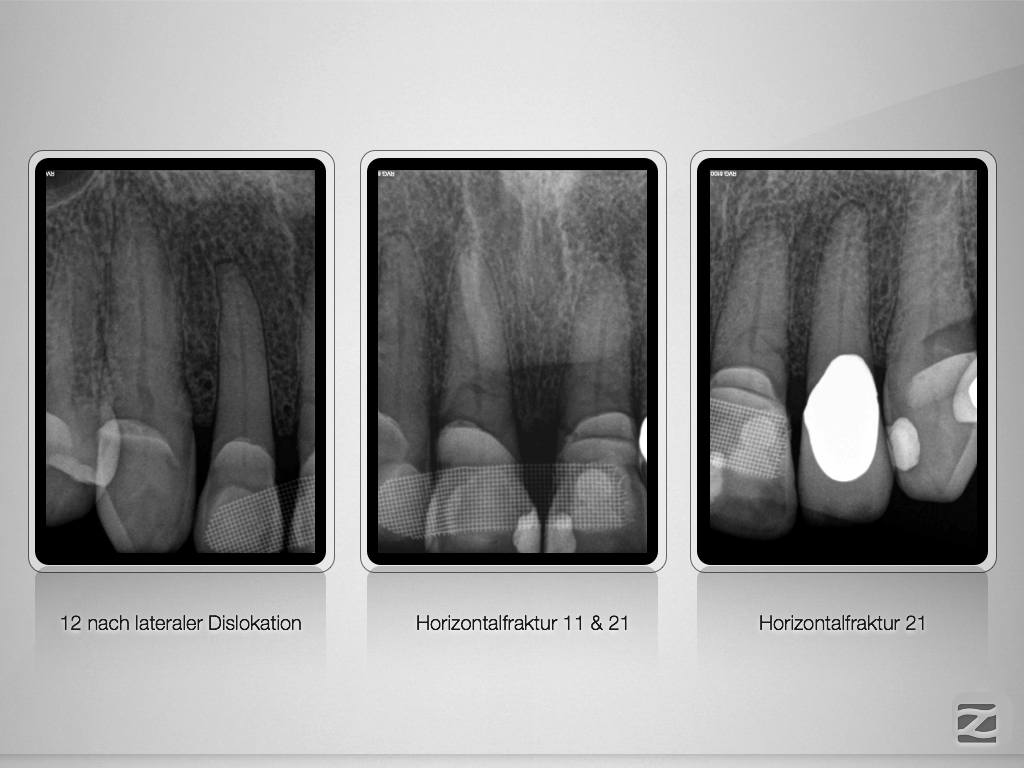

21 11 D.001

Horizontalfraktur x 2